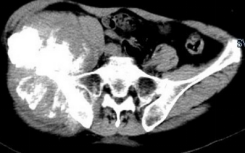

术前影像

穿刺活检提示骨盆软骨肉瘤

日前,安医大一附院骨病骨肿瘤外科胡勇教授团队成功完成一例复杂骨盆Ⅰ+Ⅱ+Ⅲ+Ⅳ区肿瘤切除与3D打印组配式半骨盆假体重建手术。患者为女性,53岁,下腰痛半年余,右侧臀部膨隆,右侧下肢轻度浮肿。右侧髂棘髂窝及臀部可触及巨大肿物,压痛明显,右髋外展前屈活动受限,右侧大腿感觉麻木,右足感觉运动正常。骨盆肿瘤切除重建是骨科专业中难度极大、风险极高的手术。骨盆肿瘤约占原发骨肿瘤的3%~4%,其中以软骨系统肿瘤最为多见,其次为骨巨细胞瘤、成骨肉瘤等,儿童尤文肉瘤亦好发于骨盆。

骨盆恶性肿瘤常潜在发展,由于骨盆位置较深,肿瘤早期很难发现,从第一次出现症状到诊断明确有时需要很长时间,当出现临床症状时,肿瘤体积已较大,因而手术切除相当困难。骨盆肿瘤血供丰富,手术出血多、难度大。另外,骨盆形态特殊,解剖复杂,切除肿瘤的同时,需要重建骨盆结构和肢体功能,技术要求高。